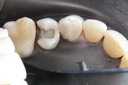

Scott Kanamori #14 pre-op

Scott Kanamori #14 caries removal

Scott Kanamori #14 prep